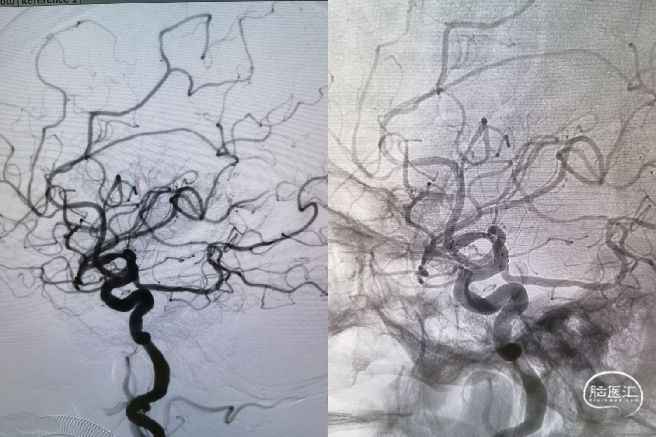

DSA提示:右侧大脑中动脉M1起始部极重度狭窄、次全闭塞,狭窄远端M1段管径约2.1mm,近端颈内动脉末端管径约3.3mm;M2段主干中度狭窄,分水岭下移;颈内动脉入路非常迂曲。

借助支架输送系统回送支架导管至支架尾端顶住再撤出支架系统,保留微导丝,观察20分钟,见血流通畅,撤出微导丝,回撤导引导管和中间导管,正侧位减影和非减影像造影提示大脑中动脉血流通畅良好,支架远近端均匀贴壁,分水岭恢复正常。

该病例的血管条件较差,近端血管严重迂曲的同时靶病变部位重度狭窄为手术医生带来了巨大的挑战。术中影像能够明显看出术者手术技巧娴熟,同时术后影像也看到前向血流明显改善接近完美。